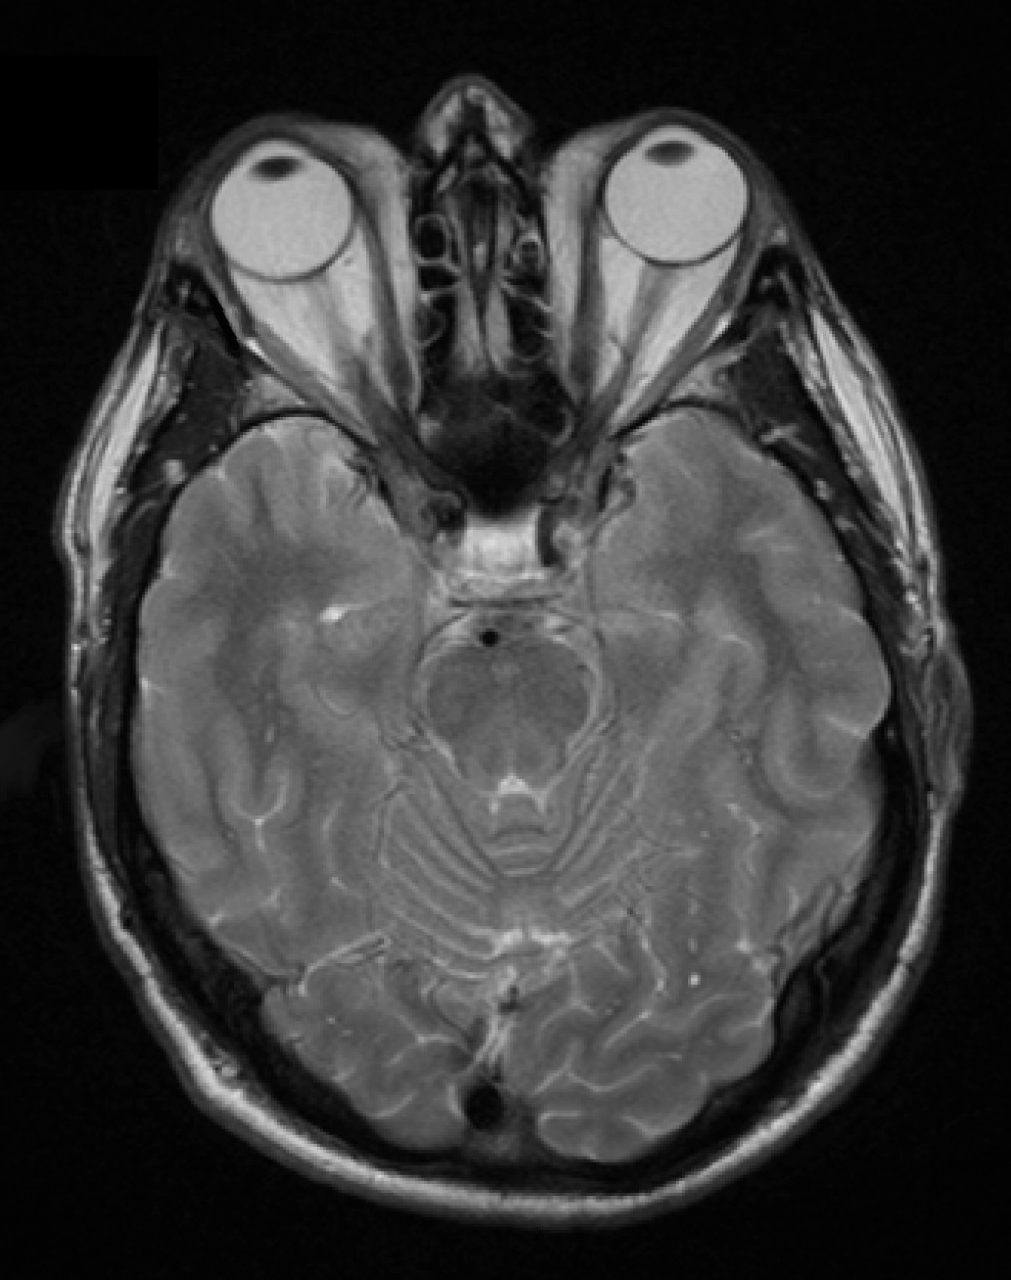

(3) 갑상샘눈병증

활성화 된 CD4+ T cell이 cytokine을 분비해 fibroblast를 자극하여 증식 및 glycosaminoglycan (GAG) 등 세포외기질 단백질 합성을 유도함 → 안와 공간에 염증세포 침윤 및 부종 발생 → 안병증 발생

• 질병 진행 시 결합조직 내 단핵구의 침윤, 안외근의 염증 및 부종, hyaluronic acid 및 chondroitin sulfate 등 친수성 GAG의 축적, 그리고 지방세포의 증가로 인해 안구 돌츨증으로 이어짐

• 이러한 변화는 안구를 전방으로 밀어내어 안구 돌출을 유발할 뿐만 아니라 외안근의 기능 장애까지 초래할 수 있음

Graves' Opthalmopathy, Wikipedia Commons